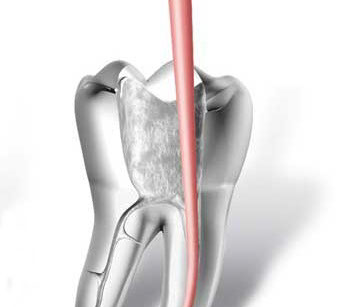

• accesso alla camera pulpare mediante frese diamantate

• asportazione della polpa e sagomatura dello spazio endodontico con strumenti meccanici (in nichel-titanio), con l'ausilio della detersione del canale radicolare (acqua ossigenata, ipoclorito di Sodio, calcio-chelanti)